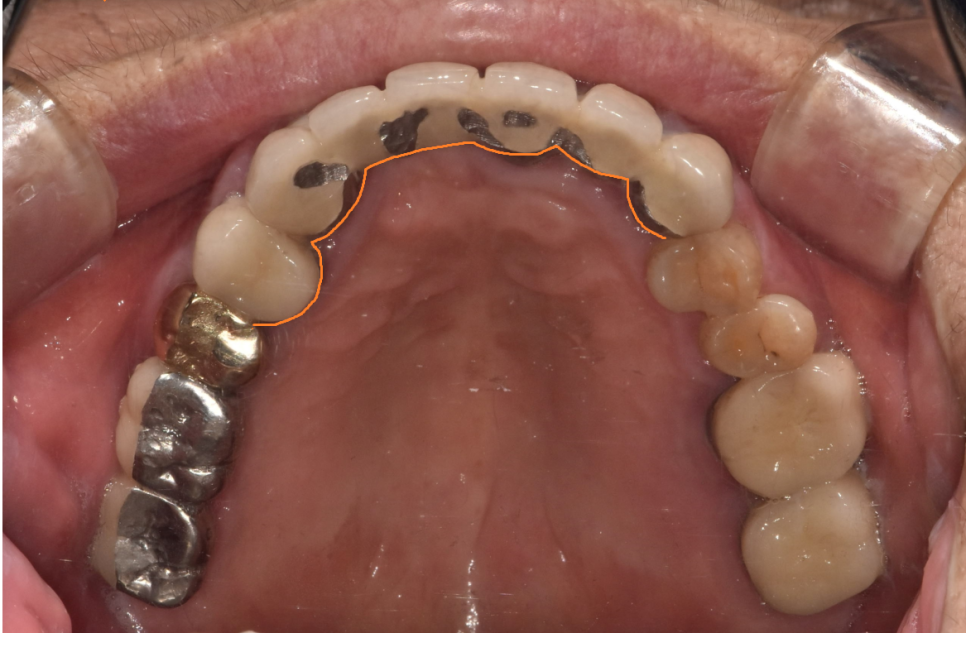

240315

앞니 브릿지 발치를 하면서 임플란트 바로 식립해드렸습니다.

이전 글에서 말씀드렸다 싶이

앞니는 뼈가 얇습니다.

그래서 뼈가 수축하기 전

발치와 동시에 수술을 하는데요.

치료기간도 단축된다는 장점이 있죠~

수술 후 일상 생활을 하셔야해서

임시 틀니를 제작

사용할 수 있게 교육해 드렸습니다.

240731

4월에 수술을 하고 3개월정도 지나

머리를 만들어 드렸는데요.

똑같이 6개를 묶은 앞니 브릿지 형태인데

임플란트는 3개를 심어 6개로 만들어 드렸습니다.